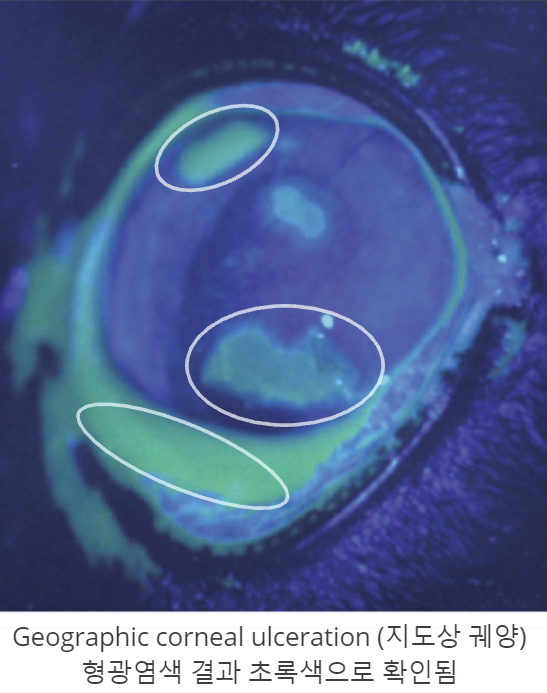

수지상 궤양(dendritic ulceration) : Herpes 초기 특징

지도상 궤양(geographic corneal ulceration)

Chronic stromal keratitis (만성 기질성 각막염)

- 각막에 만성 궤양 → 혈관 신생, 면역세포 침습(infiltration), 섬유화(fibrosis), 흉터, 색소침착 등

| Herpes (FHV) | 각막 궤양(corneal ulceration), 유산, 사산 |

- Herpes → 각막, 안구 문제 많음(각막 궤양, 결막염). / 가지모양(수지상) 궤양